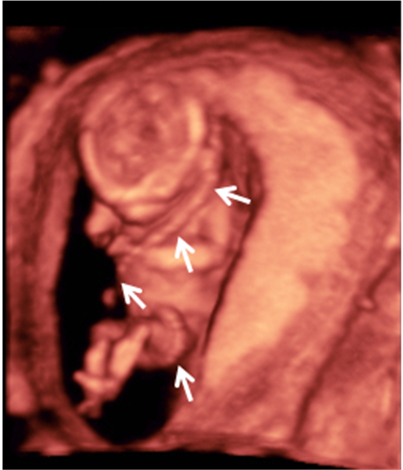

Ecografía 4D semana 11: Siameses unidos por el abdomen

La ecografía en 4D (vídeo) no deja lugar a dudas. Se trata de un embarazo de siameses de 11 semanas de gestación, que están unidos por la zona abdominal, ya que comparten una pequeña parte de hígado. La movilidad de los bebés es reducida, como vemos en las imágenes, debido a la unión de sus cuerpos. Uno de los hermanos (el de la derecha) mueve la cabeza hacia atrás, mientras las piernas se entrecruzan. Los especialistas siguen este tipo gestaciones muy de cerca y valoran la separación quirúrgica de los bebés, una vez que se produce el parto.